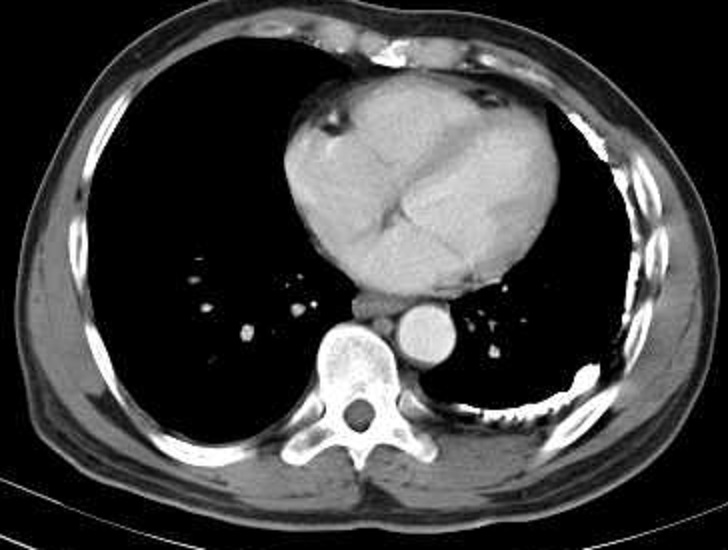

Mệme cas en coupe TDM axiale

avec aspect radiologique en plaque diffuse

hyperdensite de la plevre du poumon droit . Poumon

droit est en un peu de restrictive par la lesion de

tuberculose |